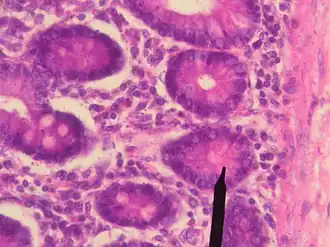

Les cellules de Paneth sont situées exclusivement au fond des cryptes intestinales.

Ce sont des cellules séreuses volumineuses, pyramidales et basophiles à cause de leur sécrétion acidophile.

Elles contiennent des grains de zymogène au pôle apical.